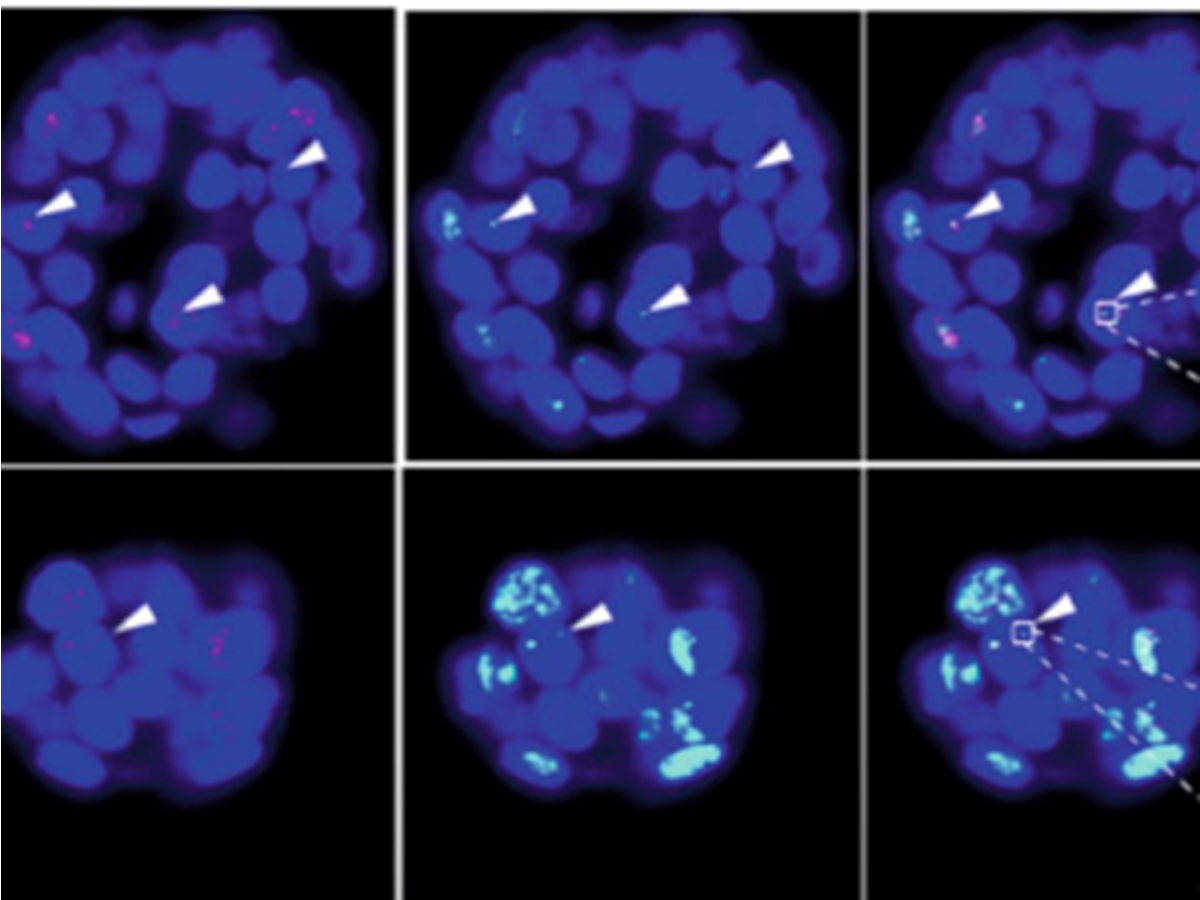

Entschlüsselung der Mechanismen der Immortalisierung mit Hilfe von Tumororganoiden

p-care Partner Stefan Schoeftner und sein Team an der Universität Trieste veröffentlichen einen wissenschaftlichen Artikel, in dem die Verwendung von Tumororganoiden Einblicke in die Mechanismen der Immortalisierung von Krebszellen gibt (Nature Communications)